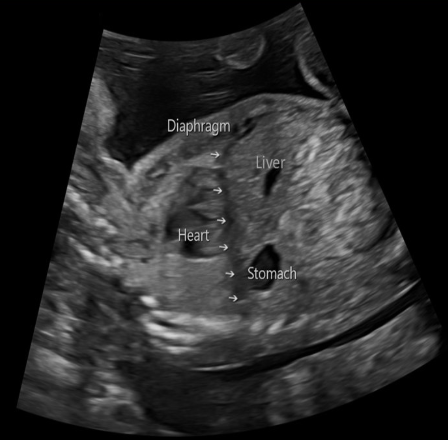

which imaging plane will best display the fetal diaphragm

a) sagittal

b) coronal

c) transverse

d) transverse oblique